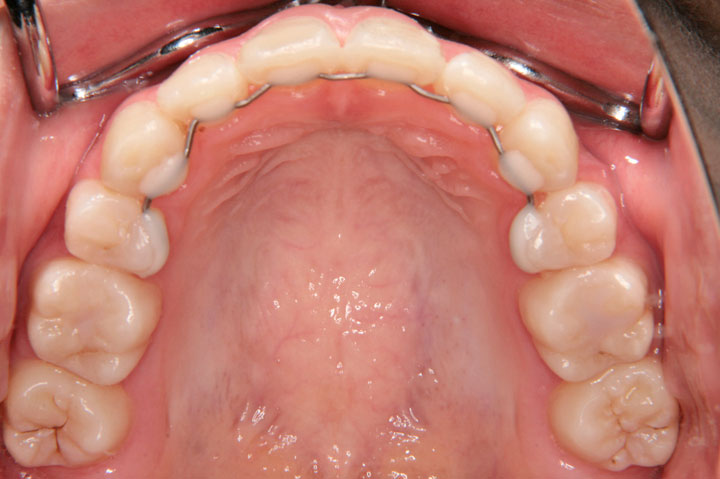

上顎前突(出っ歯)

前歯部不正(交叉咬合など)

上顎前突と叢生を気にされて来院された小学校4年生の女子の患者さんです。第一段階として、ヘッドギアーによる上顎大臼歯の遠心移動ををはかり、奥歯の関係を整えた後、上下顎小臼歯を抜歯いただきデーモンシステムで後期治療を行いました。前期治療に約1年、定期観察を経て、エッジワイズ治療に2年を要しており、その後保定に移行しております。